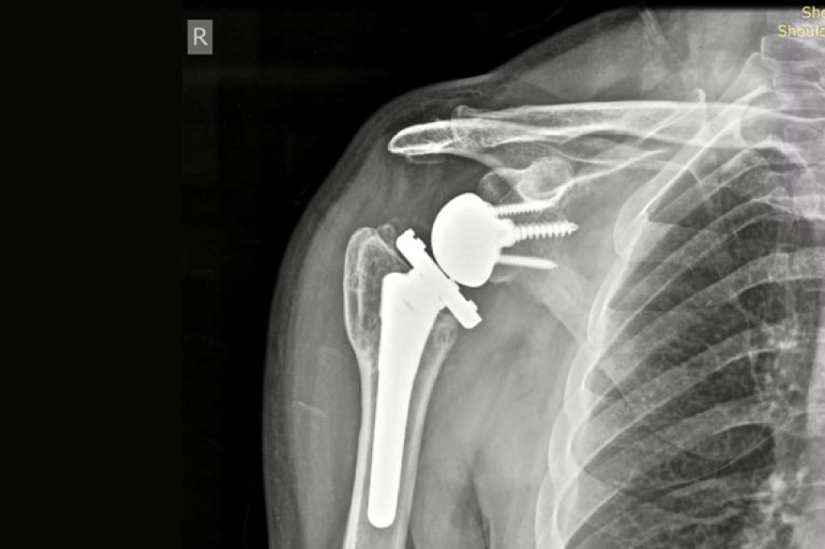

Radiografia a arătat modificări degenerative severe extinse la nivelul cartilajului articular și o afectare a structurii osoase. Diagnosticul a fost de artroză posttraumatică severă a umărului drept și necroză avansată de cap humeral. Aceste două patologii asociate au contribuit la distrugerea articulației, cu pierdere accelerată a mobilității și durere cronică invalidantă.

Dr. Cosmin Faur i-a propus o soluție inovativă, bazată pe o tehnică nouă, eficientă, dar prea puțin utilizată în România: artroplastia totală cu endoproteză inversată. Această intervenție este recomandată atunci când articulația umărului este grav afectată, iar oasele și mușchii din zonă nu mai funcționează normal, din cauza distrugerii osoase și a pierderii forței musculare. Proteza inversată oferă pacientului șansa de a mișca din nou brațul aproape normal și de a scăpa de durerea constantă.

„Artroplastia totală cu endoproteză inversată este o intervenție chirurgicală modernă, recomandată în cazurile în care articulația umărului este grav deteriorată, iar tratamentele clasice, respectiv medicamentele, infiltrațiile sau fizioterapia, nu mai dau rezultate. Se adresează în special pacienților cu artroză avansată, necroză de cap humeral, așa cum este și cazul pacientului despre care vorbim, și unde osul s-a distrus ca urmare a lipsei de vascularizare, sau în cazul unor rupturi mari ale coafei rotatorii, adică acei mușchi care mențin și ghidează mișcările umărului.

Articulația umărului este formată din capul humeral - o structură rotundă, ca o bilă, situată la capătul osului brațului - și glena, o suprafață concavă de pe omoplat, care funcționează ca o cupă. Spre deosebire de protezele clasice, proteză inversată schimbă poziția naturală a componentelor: bila artificială este fixată pe omoplat, iar componenta concavă pe osul brațului.

Această modificare permite pacienților să folosească mușchiul deltoid pentru a ridica brațul, chiar dacă mușchii principali ai umărului, nu mai funcționează corect. Rezultatul este o reducere importantă a durerii și o îmbunătățire semnificativă a mobilității. Este o procedură sigură, cu beneficii majore pentru pacienții care nu mai pot folosi umărul din cauza durerii și a blocajului articular”, explică dr. Cosmin Faur.